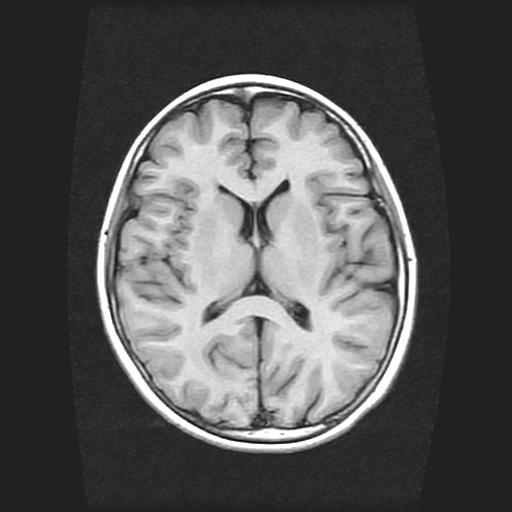

9岁女孩,三岁时诊断为癫痫,一直服丙戊酸钠,现患者一般情况良好,家长复查核磁片,看能否停药..

未见异常信号灶.

未发现异常信号。

停药要结合临床,如无发作可以停。